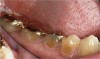

Figure  4  Possibly a combination of erosion and abrasion.

Figure 4

Figure  6  Erosion and abrasion in a xerostomic patient with Sjögren’s syndrome.

Figure 6